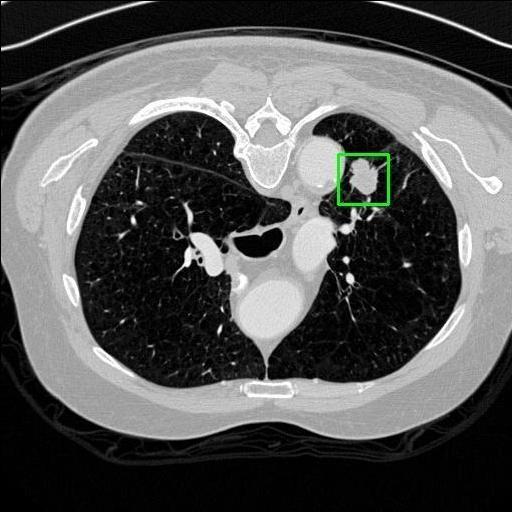

We developed an AI-based system using deep learning models for analyzing lung CT scans to detect and classify pulmonary nodules. We chose the YOLOv11 architecture for its enhanced object detection capability and adapted it specifically for medical imaging, incorporating pixel-level precision and severity classification.

Classification into three severity levels with colored bounding boxes.

Designed a severity classification system that categorizes nodules into null, moderate, and severe using colored bounding boxes, assisting in rapid clinical decision-making.